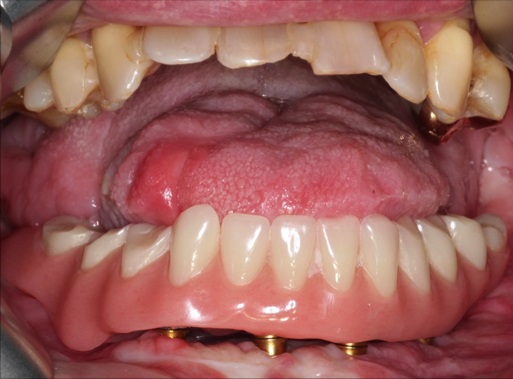

One attractive surgical possibility is the immediate placement of dental implants allowing single stage reconstruction of the jaw and dentition. However, the bony cross section is not uniform across the length of the lateral scapular border and tip, and the shape is partially twisted. The varying bone stock is not ideal for primary implant insertion in an even distribution, and may require a subsequent local bone augmentation. The most recent recommendation therefore is that the insertion of dental implants should be postponed until the preconditions have been amended.

Finally, dental implants were inserted (Fig. 8).